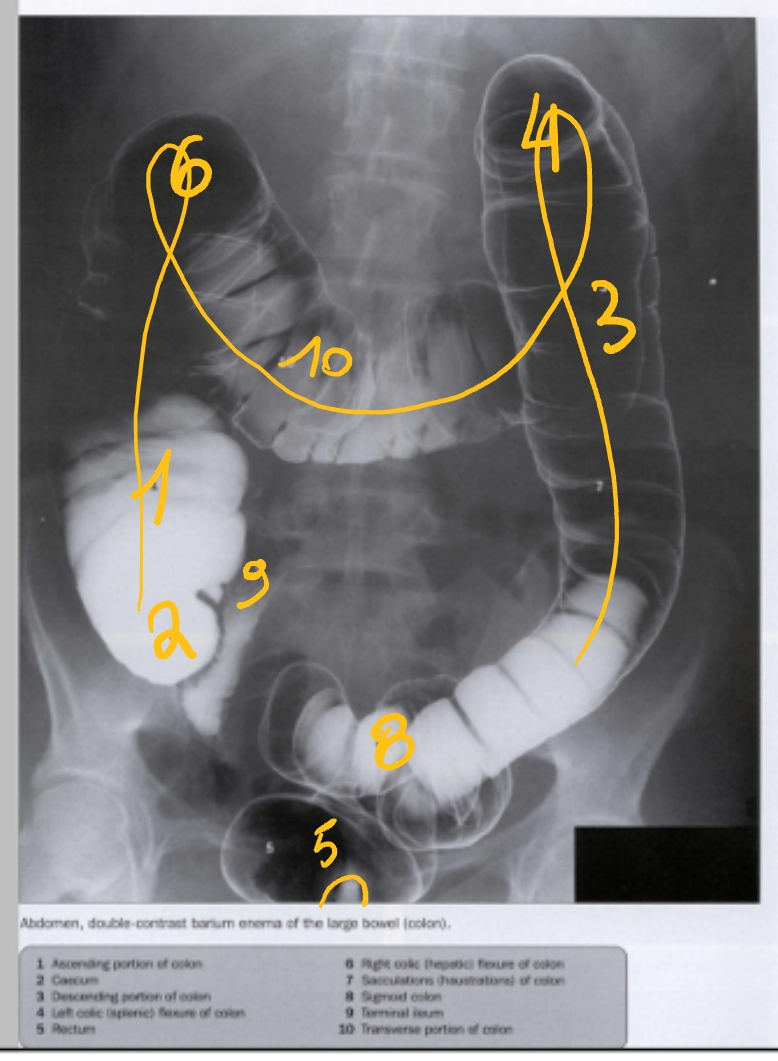

(dubbelcontrast → bariumsulfaat + lucht)

colon ascendens

caecum

colon descendens

flexura coli sinistra/ splenica

rectum

flexura coli dextra/ hepatica

colon sigmoideum

laatste ileale lis

colon transversum